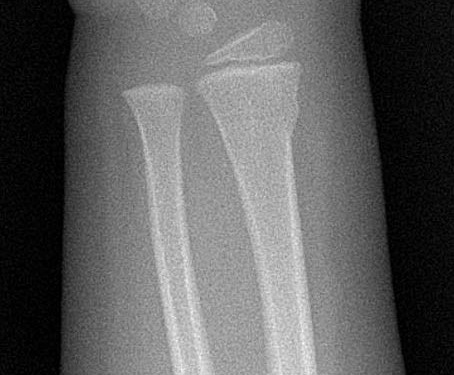

Ekstremite Kırıkları

9

distal radius

Distal radius torus kırığı